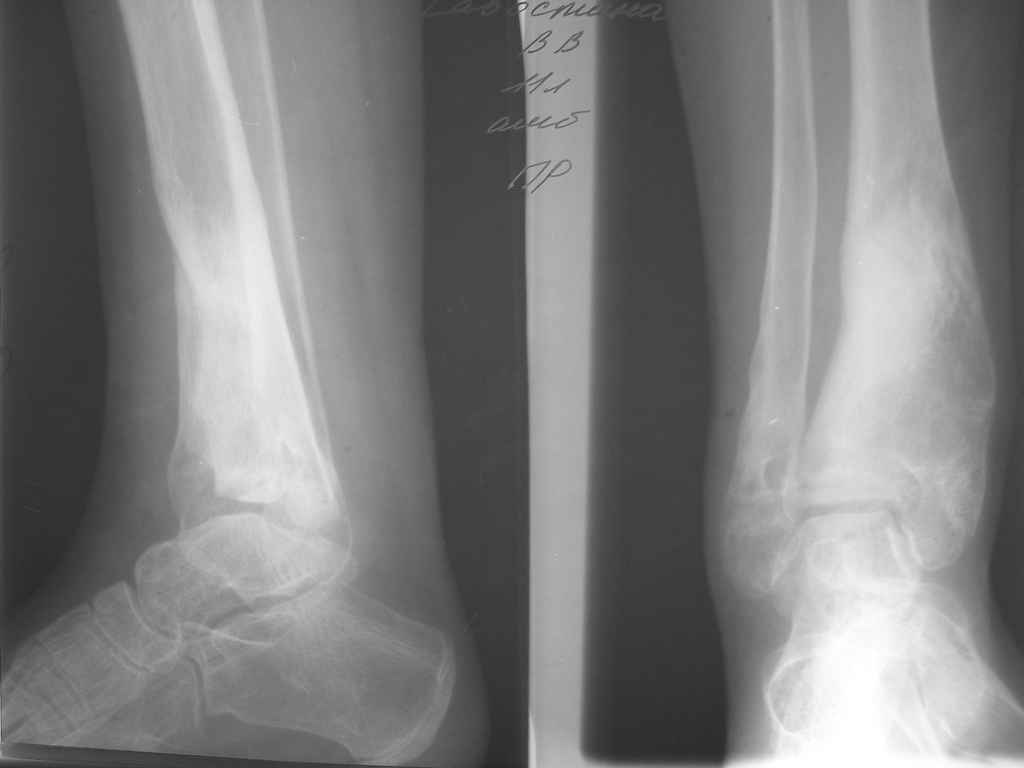

Девушка 17 лет: боли в голеностопном суставе,ограничение движений в суставе,укорочение голени,хромота Из анамнеза в раннем детском возрасте перенесла гематогенный остеомиелит дистального отдела большеберцовой кости - зона роста частично закрылась сформировалась варусная деформация голеностопного сустава + укорочение костей голени на 6 см Произведена корригирующе-удлиняющая остеотомия сначала большеберцовой,затем малоберцовой костей, устранена деформация, ликвидировано укорочение. С возрастом наросло укорочение до 3 см,клинически умеренная вальгусная деформация голеностопного сустава. Объём движений в суставе в пределах 15 град. Отмечает переодически болевой синдром, после осевой перегрузки,пользуется обувью с компенсацией, ортезом на голеностопный суставВопрос: есть ли показания для оперативного лечения: артропластика? артродез? голеностопного сустава. Какие мысли,коллеги?